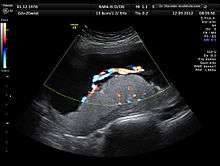

A 3D Power doppler image of vasculature in 20-week placenta